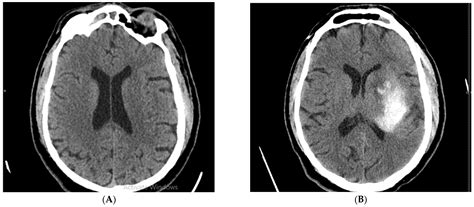

Over time, this chronic reduction in blood flow leads to small areas of injury, often referred to as white matter hyperintensities (WMH) or silent lacunar infarcts. These are essentially tiny “scars” that appear as bright spots on a T2-weighted MRI scan. Because these changes often occur slowly and in areas of the brain that are not responsible for critical motor or speech functions, many patients remain asymptomatic for years.

To evaluate these findings, clinicians typically compare imaging over time to determine if the changes are stable or progressive. Below is a simplified overview of how these changes are typically categorized in clinical settings: